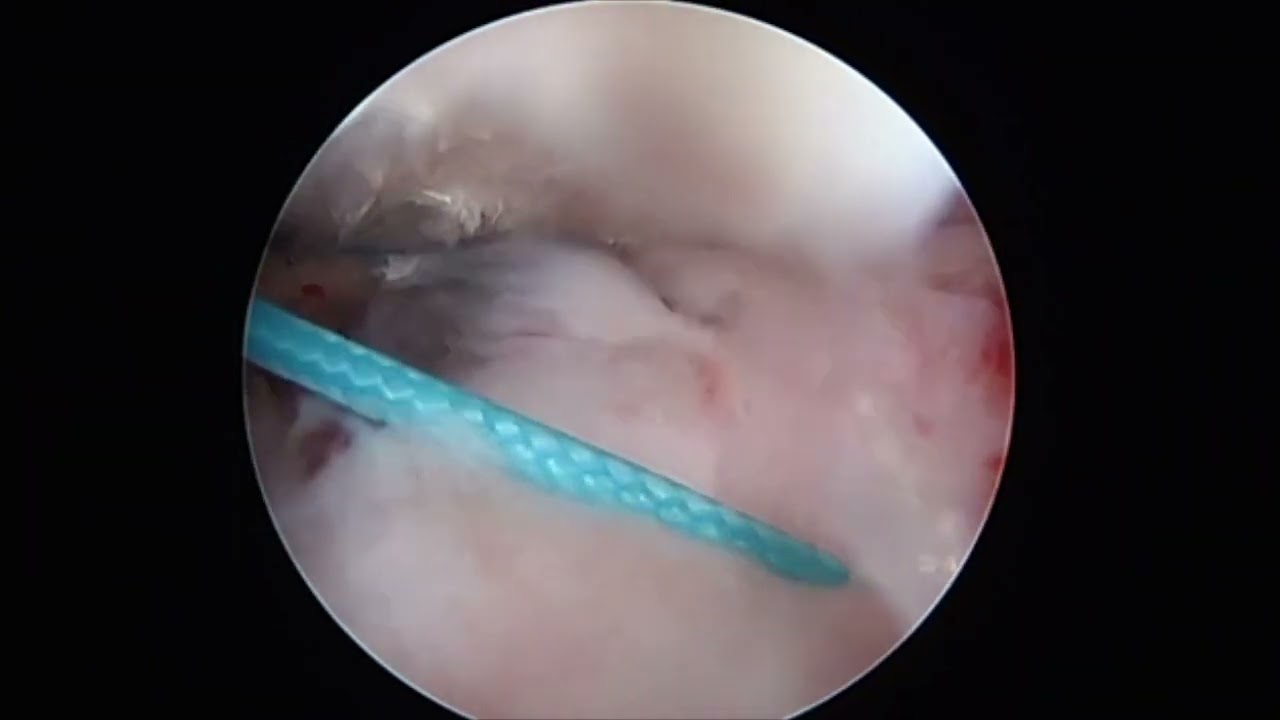

Następnie odbywałem podspecjalizację w zakresie artroskopii i rekonstrukcji barku, łokcia i kolana w Królewskim Szpitalu Ortopedycznym (The Royal Orthopaedic Hospital) w Northfield oraz w Centrum Urazowym Uniwersyteckiego Szpitala Królowej Elżbiety (Queen Elizabeth Hospital) w Birmingham.

Zdjęcia i filmy